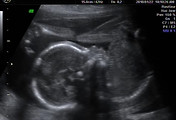

임신 12주 호야의 모습

아기의 크기가 약 8cm 정도가 되고 무게가 15~20g 정도가 되는 기간이다.

손과 다리를 움직이는 모습이 보인다. 신기하게도 잘 움직이더라~ 사지가 구분이 되니 이제 사람처럼 보인다. ^^

이 시기에 처음으로 진찰실에 같이 들어가게 되었다. 실제로 호야를 눈으로 보고 나오니 참으로 신기하고 귀엽기까지 하다. 신비한 경험이라고 할까. 머리와 몸통이 확실히 구별이 되었다.

이 시기에 검사를 하는데 태아경부투명대(NT)측정과 초음파검사로 무뇌아 진단을 한다.

먼저 태아 목부분의 투명대를 측정하여 염색체 이상에 의한 기형유무를 확인할 수 있는 시기라고 한다. 그래서 4차원 입체초음파를 하였다. 일단 합격! 통과~

그리고 한번더 찰칵! 뇌와 두개골이 잘 발될되고 있는지 확인하는 무뇌아검사를 하였다.